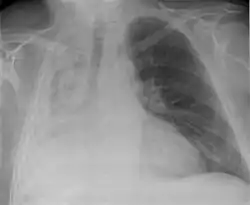

![]() انخماص في الرئة اليمنى انخماص في الرئة اليمنى | |

- الأشعة السينية للصدر (اعتِتَمام الرئة المصابة و تقلص حجمها)

أشعة الصدر السينية كافية لتشخيص حالات الانخماض المعتدة اكلينيكياً. الانخماص ما بعد العمليات الجراحية يظهر في الجزء الأدنى من الرئتين.